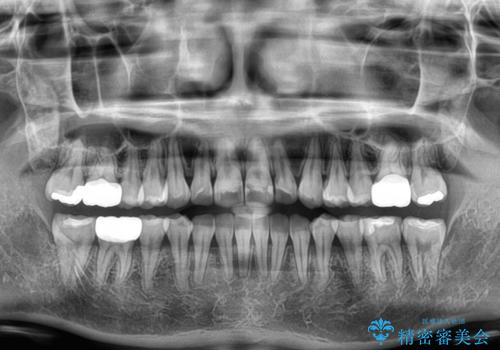

- 前歯のデコボコや、やや突出した感じを気にして来院された患者様です。

抜歯矯正を必要とするほど口元の突出感はなく、本人もそこまでは気にしていない様子でした。

お仕事柄、マウスピース装着は困難とのことで、表側のワイヤー矯正にて治療を行うこととしました。

デコボコ解消の際に、前歯が前突するリスクがあったため、舌突出癖の改善と、アンカースクリューによる加強固定を行うこととしました。

矯正治療後には奥歯の銀歯やむし歯をセラミックやゴールドにて治療を行い、大変整った口腔環境へと改善さ。れました